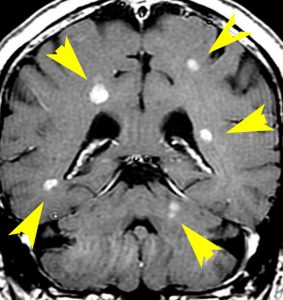

典型的な転移性脳腫瘍(単発)のMRI

腺癌の左前頭葉転移です。左のガドリニウム造影剤を使った画像では腫瘍が白く写っています。腫瘍の内部が一部壊死しているので黒っぽく見えます。右はフレア画像です。腫瘍の周囲の脳が腫れて脳浮腫(白く滲むようなところ)を生じています。

開頭手術で摘出した半年後の画像です。腫瘍は再発していなくて,脳の腫れも引いています。転移が発見された時には,見当識障害などの左前頭葉症状が強かったし,摘出がとても簡単な場所だったので手術しました。線状皮膚切開・小開頭ですから1時間くらいの簡単な手術です。でも,26mmくらいでしたから,定位放射線治療も可能なものでした。この患者さんは幸いなことに半年で再発していませんが,開頭手術による摘出だけだと同じ場所からまた再発することもあり,それから放射線治療を加えなくてはならないこともあります。個々の判断は難しいのですが,基本的には開頭手術より定位放射線治療のほうがいいと考えて下さい。